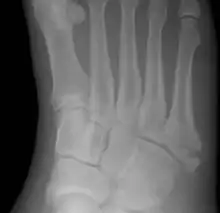

| Jones fracture as seen on Xray | |

A Jones fracture is a broken bone in a specific part of the fifth metatarsal of the foot between the base and middle part[8] that is known for its high rate of delayed healing or nonunion.[4] It results in pain near the midportion of the foot on the outside.[2] There may also be bruising and difficulty walking.[3] Onset is generally sudden.[4]

The fracture typically occurs when the toes are pointed and the foot bends inwards.[6][2] This movement may occur when changing direction while the heel is off the ground such in dancing, tennis, or basketball.[9][10] Diagnosis is generally suspected based on symptoms and confirmed with X-rays.[3]

Diagnostic X-rays include anteroposterior, oblique, and lateral views and should be made with the foot in full flexion.